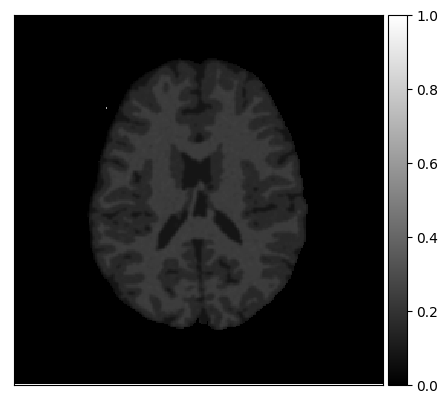

In order to test the proposed method on real data, we use the publicly available training data (5 subjects) from the MRBrainS challenge444http://mrbrains13.isi.uu.nl/Figure. The acquisition parameters used for simulating the Brainweb3.0T are based on the MRBrainS acquisition protocol (3.0T scanner, gradient-echo, B0 = 3.0T, = flip angle, TE = 4.5ms, and TR = 7.9ms). Figure 5(c) shows an example of an MRBrainS scan. Again, a brain mask is used to strip the skull.

Examples of the segmentation results on one of the target test images are shown in Figure 8 for experiment 2.1, Figure 9 for experiment 2.2, and Figure 10 for experiment 2.3. Examples are shown after using 1 target patch per tissue for training, and after using 100 target patches per tissue for training. The results show that only the mrai-net classifier is able to predict a segmentation that approaches the ground truth with only 1 target patch per tissue for training (error for experiment 2.1 = 0.269, experiment 2.2 = 0.403, experiment 2.3 = 0.320), while the source and target classifiers cannot (source error for experiment 2.1 = 0.667, experiment 2.2 = 0.653, experiment 2.3 = 0.435; target error for experiment 2.1: 0.591, experiment 2.2: 0.614, experiment 2.3 = 0.596). After using 100 patches the source and target classifiers can predict a gross segmentation of WM, GM and CSF (source error for experiment 2.1 = 0.213, experiment 2.2 = 0.384, experiment 2.3 = 0.363; target error for experiment 2.1: 0.205, experiment 2.2: 0.368, experiment 2.3 = 0.368), but the mrai-net classifier prediction shows more details and a lower tissue classification error (error for experiment 2.1 = 0.111, experiment 2.2 = 0.276, experiment 2.3 = 0.284).